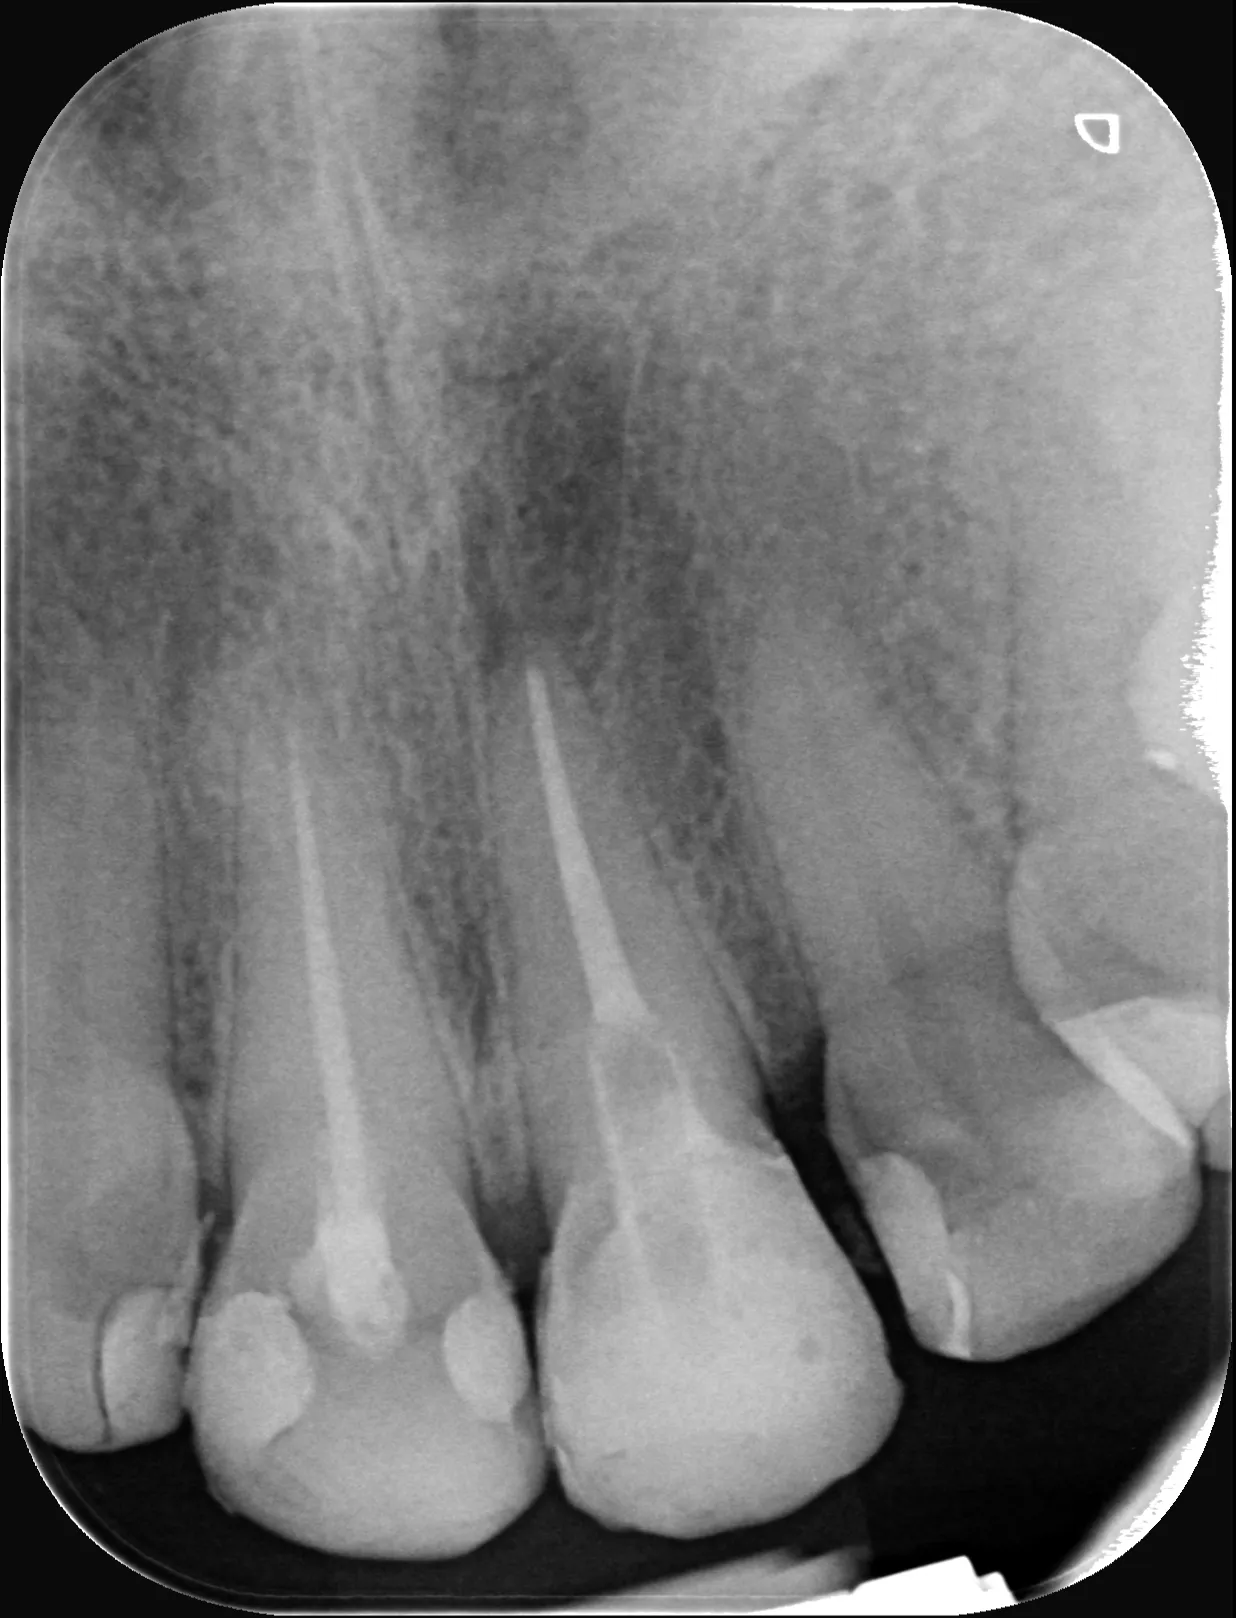

0 – Radiografie inițială

20 – Radiografia de control imediat după finalizarea tratamentului